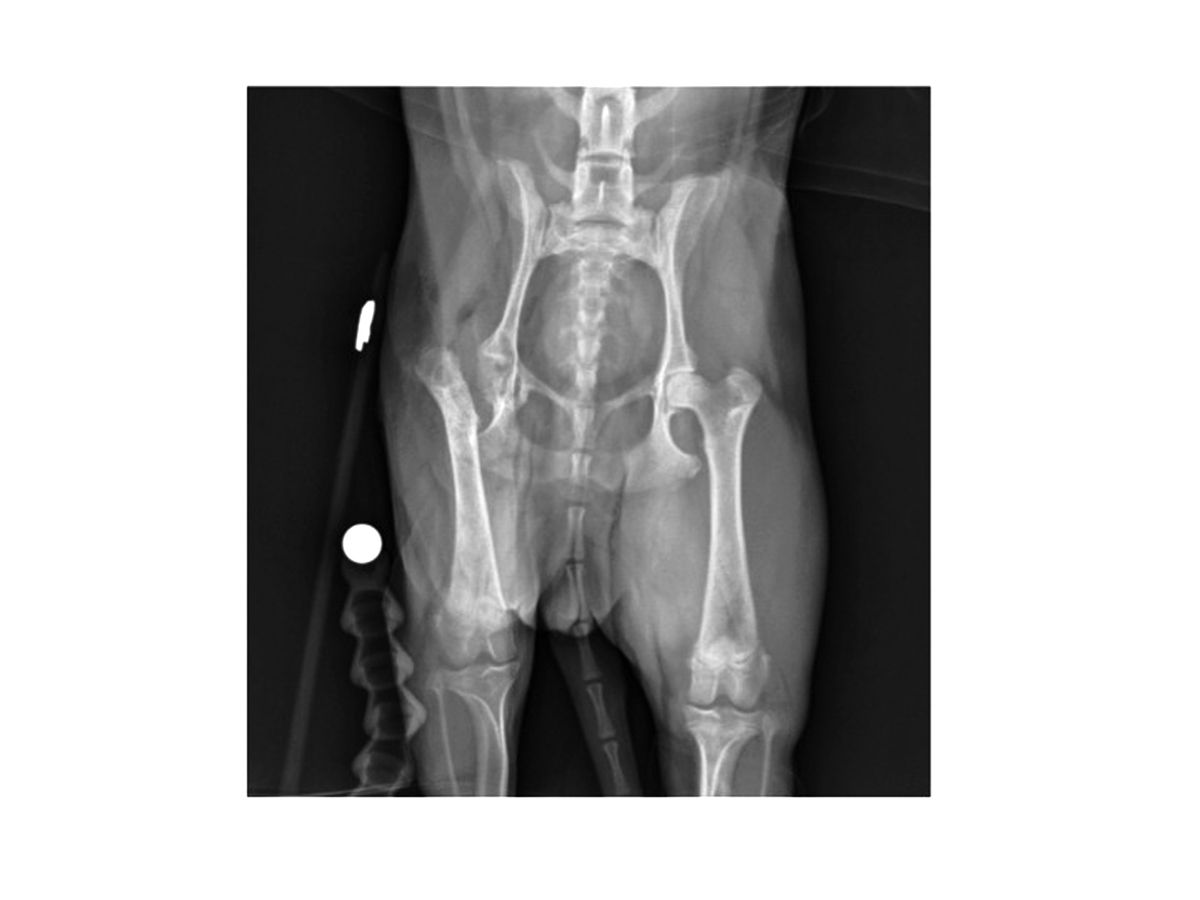

Même si l’examen clinique et l’anamnèse évoquent fortement une MLPC, des radiographies sont généralement réalisées pour confirmer le diagnostic. Initialement, des zones de lyse et de déminéralisation peuvent être présentes en région sous-chondrale de la tête et du col du fémur (Figure 1). La maladie progressant, un tassement franc de la tête et du col peut s’observer (Figure 2). Dans les stades plus avancés, des signes de reminéralisation et de cicatrisation osseuse peuvent être présents. Des anomalies arthrosiques secondaires peuvent s’observer, incluant la formation d’ostéophytes (notamment sur le pourtour acétabulaire dorsal et la tête fémorale) et l’aplatissement de la tête fémorale.

Radiographie d’un chien montrant des signes caractéristiques précoces de MLPC. La flèche indique des zones de déminéralisation débutante.

Figure 1. Radiographie d’un chien montrant des signes caractéristiques précoces de MLPC. La flèche indique des zones de déminéralisation débutante.© Darryl L. Millis